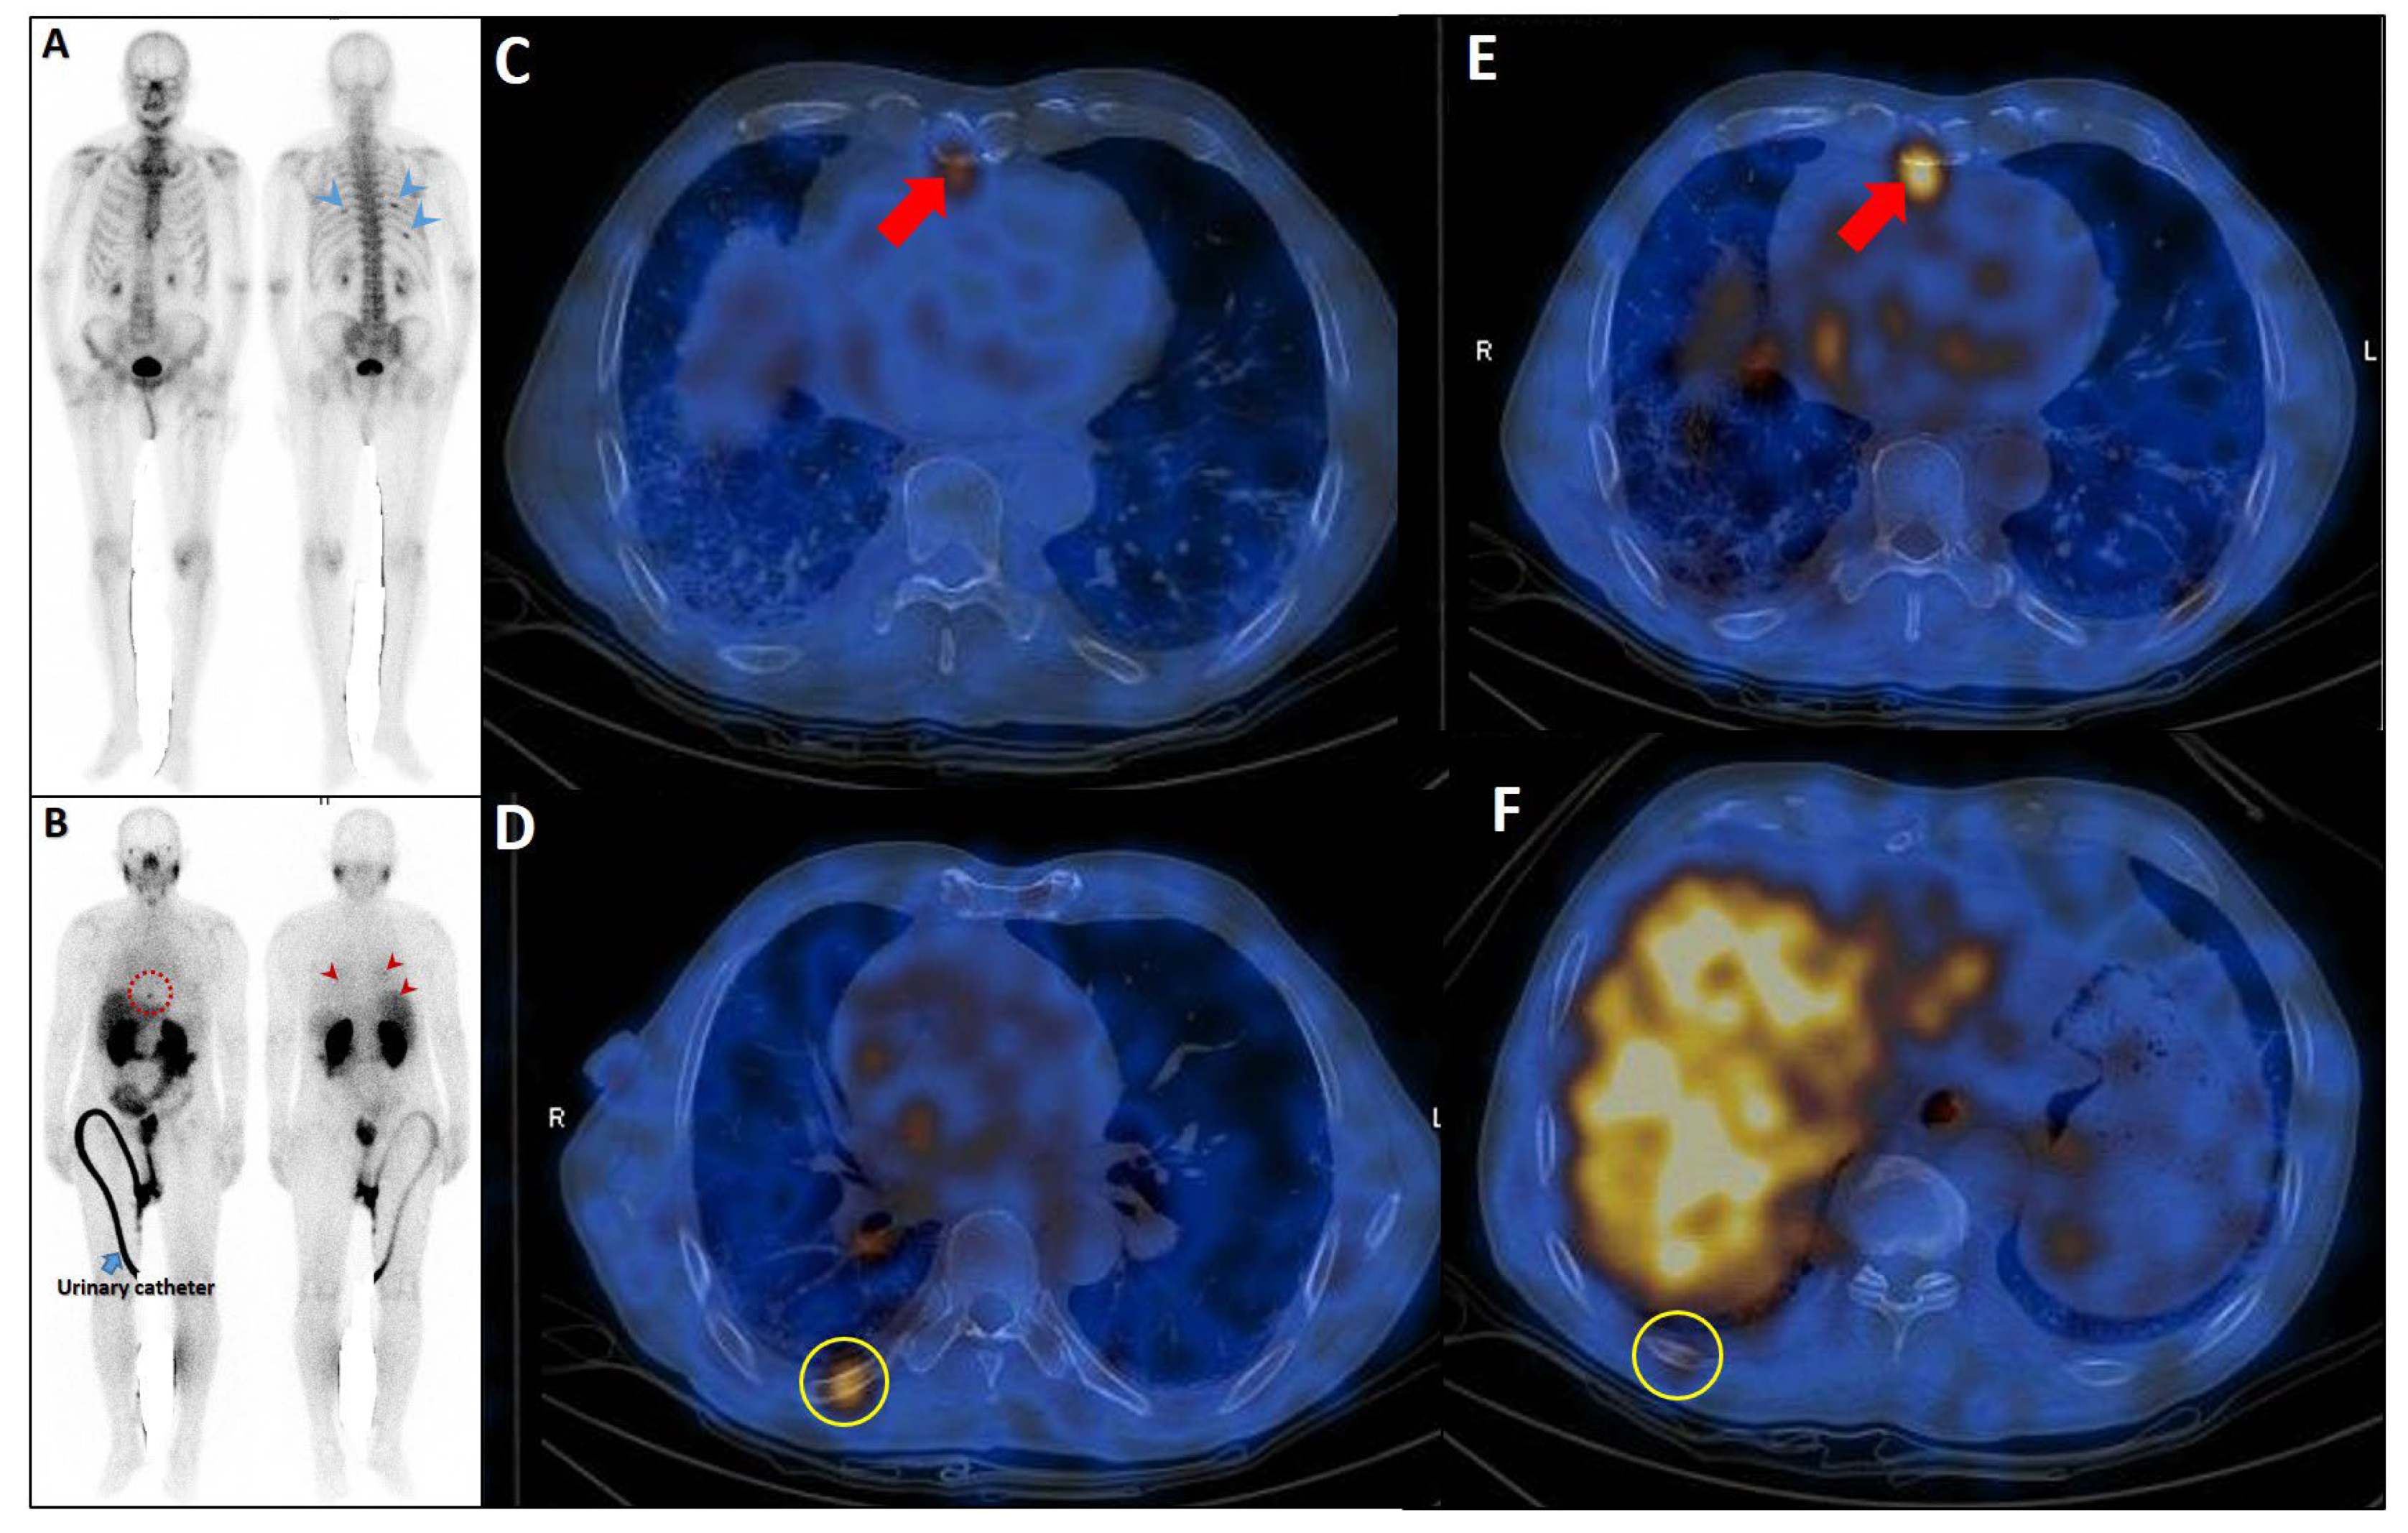

| Factor | Description | Benign Characteristics | Metastatic Characteristics | Diagnosis Utility | Pitfalls |

|---|---|---|---|---|---|

| Radiotracer Uptake Intensity | Standardized uptake value maximum on PSMA PET/CT | Low-moderate (<10); often < liver uptake | High (>10); typically > liver uptake | Predicts malignancy likelihood; guides radioligand therapy | Tracer variability (18F-PSMA-1007 higher unspecific uptake); no standardized cutoff |

| Number of Lesions | Number of PSMA-avid rib lesions | Solitary (98% benign if isolated) | Multiple (97–98% associated with polymetastatic disease) | Indicates disease extent; solitary lesions often benign | Rare isolated metastases (2–3%); needs correlation with other sites |

| Location | Rib lesion site | Posterior ribs (often degenerative) | Anterior/lateral ribs (higher malignancy risk) | Guides biopsy prioritization | Limited data on site-specific malignancy rates |

| CT Morphology or Bone Scan | Structural features on CT (lytic or sclerotic) | Normal or degenerative | Lytic or sclerotic lesions; cortical disruption | Enhances specificity when combined with PSMA uptake | Non-specific findings |

| Patient-Specific Factors | Patient-specific factors (such as PSA and Gleason score) | Low PSA (<10 ng/mL); Gleason <7 | High PSA (>20 ng/mL); Gleason ≥8 | Contextualizes imaging; high-risk features suggest metastases | Non-specific; overlap in early disease |

| Changes Over Time | Longitudinal changes on serial PSMA PET/ | Stable SUVmax, no new lesions; often degenerative or post-traumatic | Increasing SUVmax (>20% rise), new lesions, or morphological progression | Indicates disease progression; guides therapy adjustment | Requires serial imaging; limited data on optimal intervals; benign changes (such as healing fractures) may mimic progression |

| Tracer Type | PSMA ligand used (18F-PSMA-1007 vs. 68Ga-PSMA-11) | 18F-PSMA-1007: higher unspecific bone uptake (20% equivocal) | 68Ga-PSMA-11: lower unspecific uptake; higher specificity | Influences diagnostic accuracy; 68Ga-PSMA-11 preferred for rib lesions | 18F-PSMA-1007 increases false positives; protocol variability |